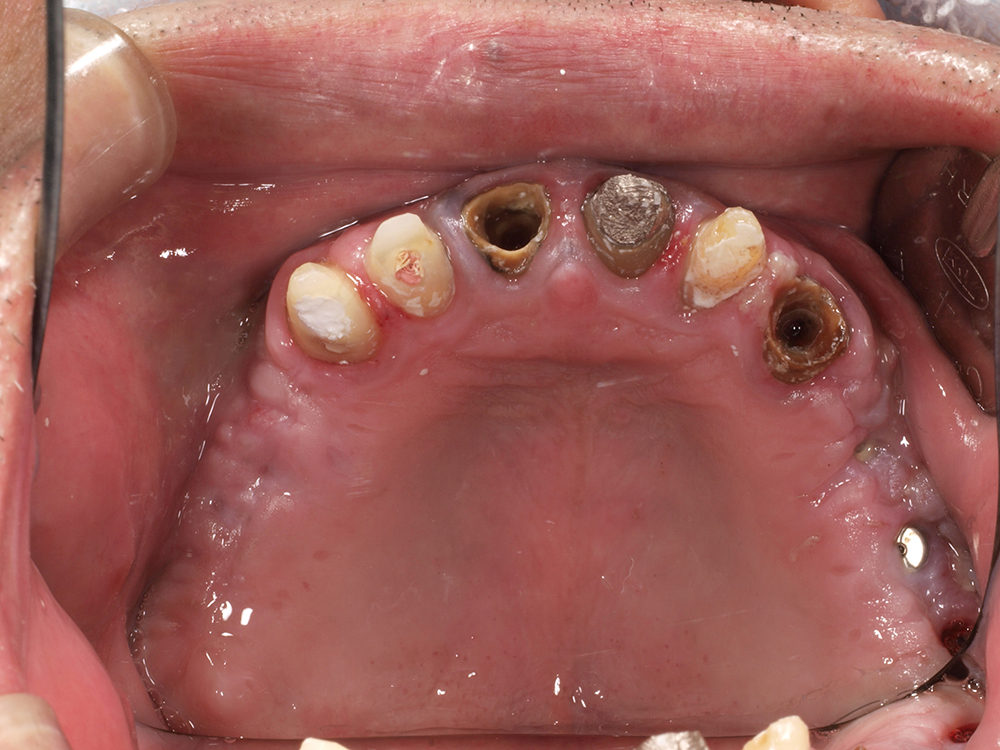

53歳 男性

- 主訴

- 全然噛めない。上の歯が取れてきた

- 処置内容

- 上顎:8本 下顎:2本

- 治療費用

- 上顎:約320万円(税込)、下顎:約160万円(税込)

- 治療期間

-

上顎:1年(仮歯まで8か月)

下顎:8か月(仮歯まで5か月)

- リスク

- 上部構造物、仮歯の破折、術後の腫れ(3日)、人工歯根脱落リスクがあります